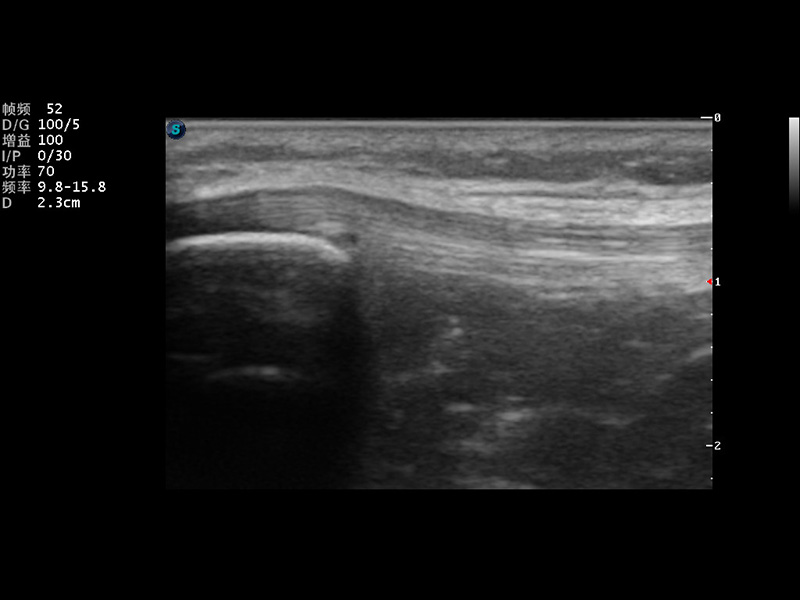

S9便携式彩色多普勒超声诊断仪是乐玩lewin国际研发的高端便携彩超设备,外观设计新颖、产品性能卓越。S9在便携超声领域采用了突破传统的触摸屏交互设计,并以先进的软件硬件技术和设计理念,为您带来清晰的图像质量、稳定的工作性能和便捷的操作体验。

μ-Scan微米成像